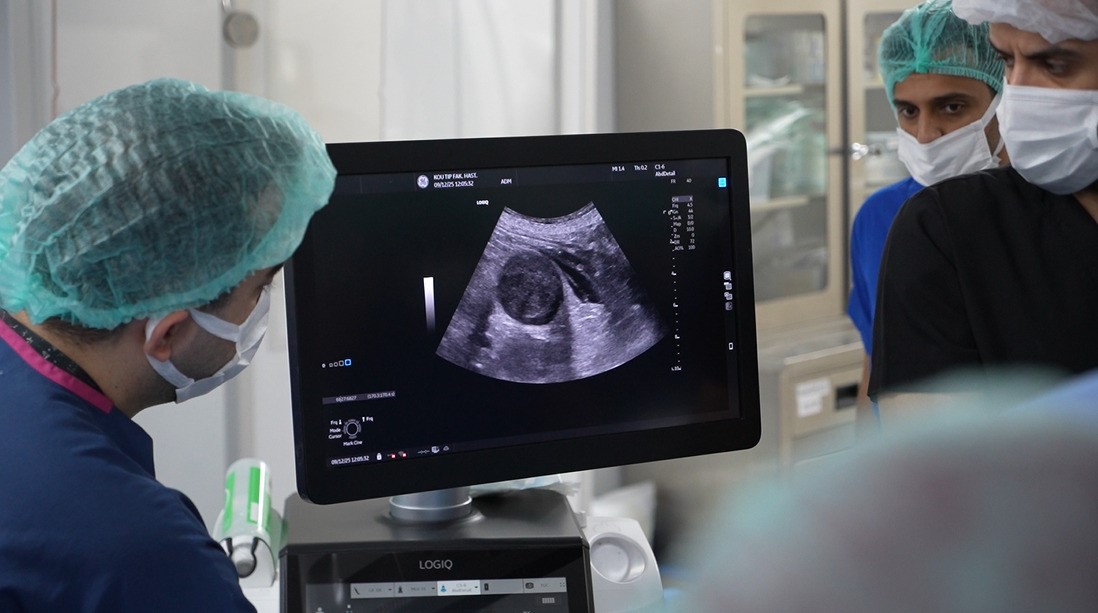

Girişimsel Radyoloji Bilim Dalı Öğretim Üyesi Doç. Dr. İsa Çam koordinesinde gerçekleşen etkinlik kapsamında, karaciğer, böbrek, tiroit ve paratiroit tümörlerinde uygulanan ve halk arasında “iğne ile yakma” olarak bilinen tedavi yöntemi, canlı vakalar eşliğinde katılımcılara gösterildi. Yaklaşık yarım saat süren operasyonla tümörün iğne deliğinden girilerek yakılması işlemi, yabancı hekimler tarafından ilgiyle takip edildi.

Doç. Dr. İsa Çam, görüntüleme yöntemleri eşliğinde yaptıkları işlemleri “iğne deliğinden ameliyat” olarak tanımlayarak, şunları kaydetti:

Artan talepler üzerine iki günlük workshop düzenlediklerini belirten Çam, “Workshopun ana amacı karaciğer, böbrek, tiroit ve paratiroit tümörlerinde ameliyatsız termal ablasyon yöntemlerini canlı vakalar eşliğinde göstermek. Bu kapsamda katılımcı hekimlere tiroit termal ablasyon işlemlerinin canlı uygulamasını gösterdik. Bölüm olarak oldukça tecrübeliyiz. Son iki yılda 500-600 vaka gerçekleştirdik. Bu bilindiği için hekimler eğitim talep ediyor. Üniversite yönetiminden ve hastalarımızdan izinleri alarak bu organizasyonu yaptık, geri dönüşler çok olumlu” dedi.